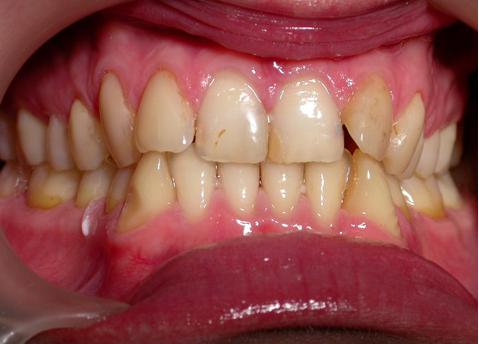

Пациент обратился с диагнозом индивидуальная макродентия.

Диагностика дополнительно выявила:- тенденцию к формированию мезиальной окклюзии,

- сужение и укорочение зубных рядов,

- ретрузию верхних центральных резцов,

- мезиальное смещение боковых отделов нижнего зубного ряда,

- ретрузию нижних резцов,

- множественные аномалии положения зубов.

Результат получен спустя 18 месяцев после начала лечения